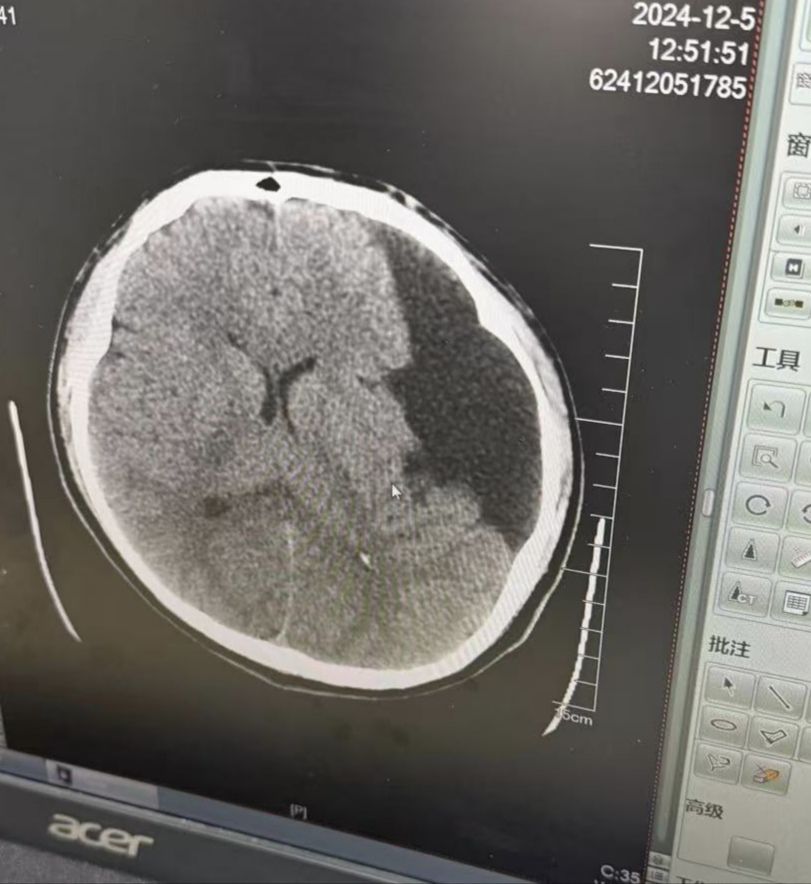

其实没什么症状就是右手有时候会抖,紧张的时候抖得很厉害,女朋友学医的就让我去查一下。结果脑子里有个4公分的蛛网膜囊肿[s:ac:呆]好在医生说没事以后定期复查就可以。本来都定好了51订婚下半年结婚,现在就特别担心未来丈人和丈母娘的态度[s:ac:愁]。

昨天已经跟对方父母汇报了这个事,约了周天一起去找专家看看。自己爸妈不在身边怕他们担心还没说。唉怎么这么糟心,万能的潭友们借我点力量吧[s:a2:哭] [img]https://img.nga.178.com/attachments/mon_202504/08/-4qiozQ2v-j5hsZbT1kSgb-sg.jpg[/img] [img]https://img.nga.178.com/attachments/mon_202504/08/-4qiozQ2v-8md0K24T1kShs-137.jpg[/img]